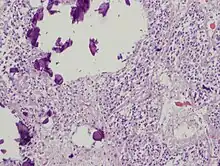

The pineal body in humans consists of a lobular parenchyma of pinealocytes surrounded by connective tissue spaces. The gland's surface is covered by a pial capsule.

The pineal gland consists mainly of pinealocytes, but four other cell types have been identified. As it is quite cellular (in relation to the cortex and white matter), it may be mistaken for a neoplasm.[19]